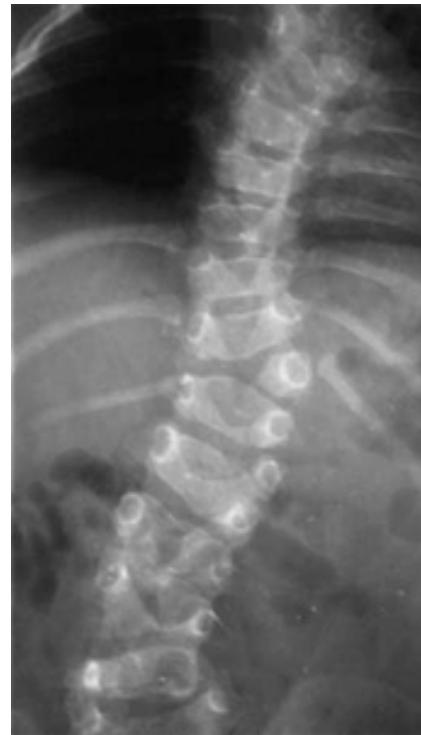

Degenerative Spondylolisthesis

- Definition: Common degenerative condition characterized by subluxation of one vertebral body anterior to the adjacent inferior vertebral body with intact pars

- Demographics: Most common in females over 40 years of age, at the L4-5 level

- Diagnosis: Lateral radiographs; flexion and extension lateral lumbar radiographs can identify degree of instability

- MRI: Helpful for central or foraminal stenosis

Treatment:

- Nonoperative: Trial with NSAIDs and physical therapy

- Surgical: Indicated for progressive disabling pain that has failed nonoperative management, and/or progressive neurological deficits